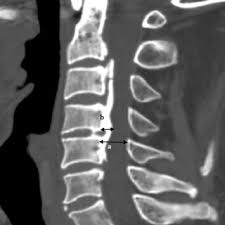

Image Type Cervical Spine X-Ray CT Scan MRI Scan Atlantodental Interval (ADI) Basion–Axial Interval (BAI) Basion–Dens Interval (BDI) Canal Occupying Ratio (COR) Clivo-Axial Angle Facet Joint Overlap (Percent Overlap Method) Facet Joint Step-Off/Dislocation Grabb-Oakes Measurement (pB - C2 line) Occipital Condyle–C1 Interval (CCI) Posterior Atlantodental Interval (PADI) Power’s Ratio Sagittal Vertical Axis (SVA) Segmental Angle Translation on Sagittal Reconstruction